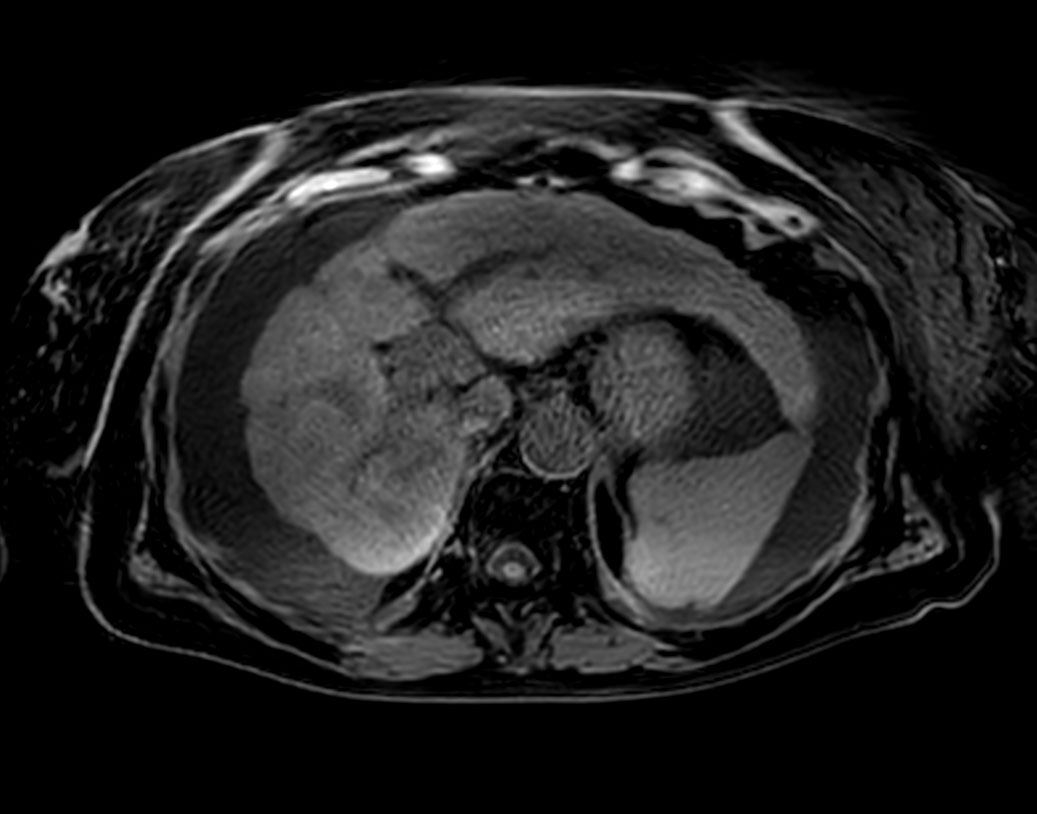

Axial T2w TSE